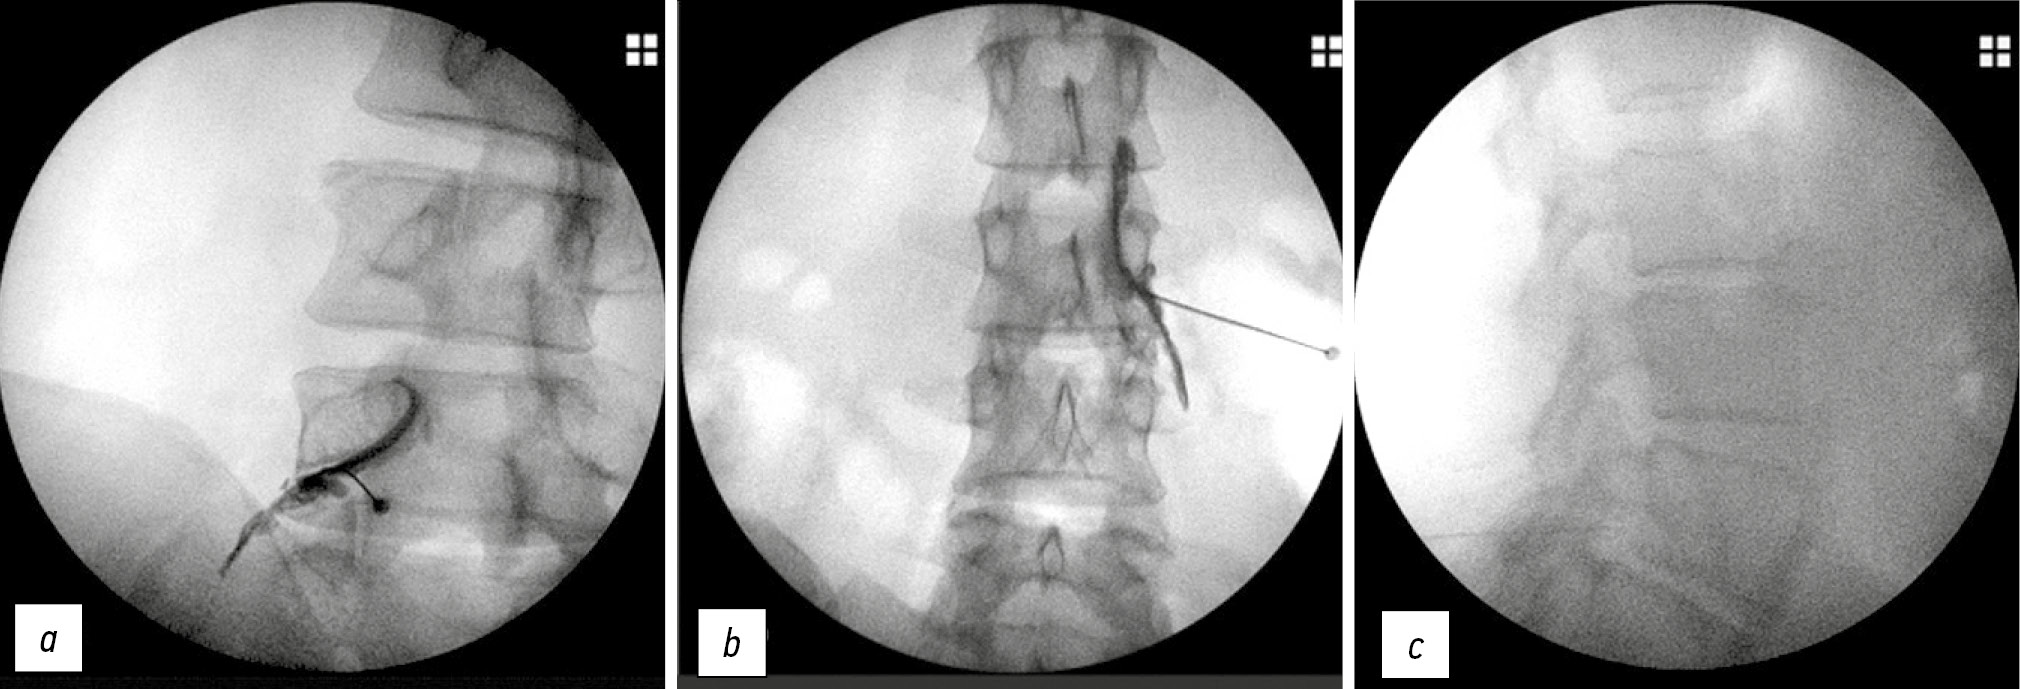

Пациент находится в положении лежа на животе с подушками под животом для уменьшения поясничного лордоза. Целевая область идентифицируется с помощью тени в виде скотч-терьера (Scotty dog shadow). Дуга флюороскопа должна быть отрегулирована и повернута на 15–30º в сторону места пункции, чтобы визуализировать тень скотч-терьера (рис. 7а), а верхний суставной отросток можно было видеть в середине межпозвонкового диска.

Рис. 7. Положение иглы при трансораминальном субпедикулярном ведении: а – в проекции 20°, b – в передне-задней проекции, c – в боковой проекции / Fig. 7. Needle position in transoraminal subpedicular control. а – in projection 20°, b – in anterior-posterior projection b – in lateral projection

После обработки операционного поля раствором антисептика игла продвигается к области inferolateral interarticularis (безопасный треугольник) для верхнего межпозвонкового отверстия. Когда кончик иглы достигает нижнелатеральной границы (угол между нижней челюстью и шеей скотч-терьера), дуга флюороскопа должна быть повернута в боковую проекцию. Иглу постепенно необходимо продвигать к передней и верхней сторонам межпозвоночного отверстия. Когда игла достигнет конечного места, должен быть проведён аспирационный тест для проверки обнаружения крови, далее вводится 1 мл йодсодержащего контрастного вещества под рентгеноскопией в режиме реального времени, чтобы определить, было ли введено вещество в переднее эпидуральное пространство.

Для попадания в треугольник Камбина (перед основанием уха скотч-терьера) игла направляется к латеральной нижней части верхнего суставного отростка параллельно рентгеновской проекции, далее, упираясь в суставной отросток, игла направляется латерально и продвигается на 2–3 мм. Затем игла вводится медиально в направлении 5 часов верхней ножки на переднезаднем плане (рис. 8). Далее вводится 4 мл препарата (0,5% лидокаин 2 мл + дексаметазон 8 мг).

Рис. 8. Расположение иглы при ТФ введении через треугольник Камбина / Fig. 8. Location of the needle during transforaminal administration through the Kambin triangle